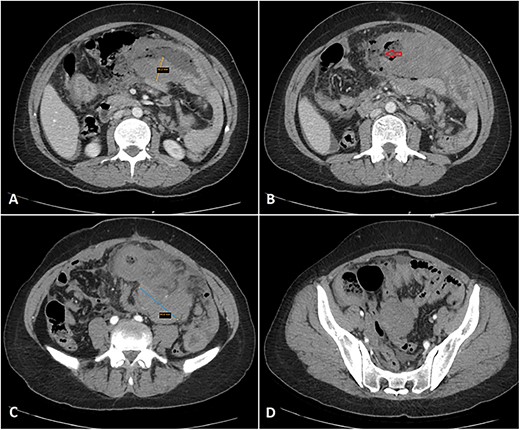

The patient presented to the emergency department with 2 h of sudden-onset abdominal pain, vomiting, diarrhea, nausea, and loss of appetite. Her vital signs were a blood pressure of 126/78 mmHg, a pulse of 107 bpm, and a temperature of 38.8°C. Abdominal examination found diffuse tenderness and distinction with a positive rebound test. The laboratory tests showed abnormally elevated inflammatory markers (CRP = 247 mg/L, WBC = 9500 cells/mm3, PMNs = 88%). An abdominal contrast computed tomography imaging showed wall thickening of the jejunum, ileum, and adjacent mesenteric lymphadenopathy, suggesting a Crohn’s flare (Fig. 1).

Multiple axial cuts of the patient’s abdomen CT scan with IV contrast are shown. Extensive bowel wall thickening up to 3 cm is noted, involving a long segment of small bowel loops in the left abdomen (jejunal loops) with a gray pattern of enhancement (A). Additionally, a wall defect/perforation is seen with the surrounding pneumoperitoneum and spillage of fecal material within the peritoneal cavity (B). Associated multiple enlarged adjacent mesenteric lymph nodes are also demonstrated, forming a large mass-like lesion with surrounding fat stranding (C). Moreover, mild wall thickening involving another short segment of small bowel loops in the right abdomen (ileal loops) is also noted (D).